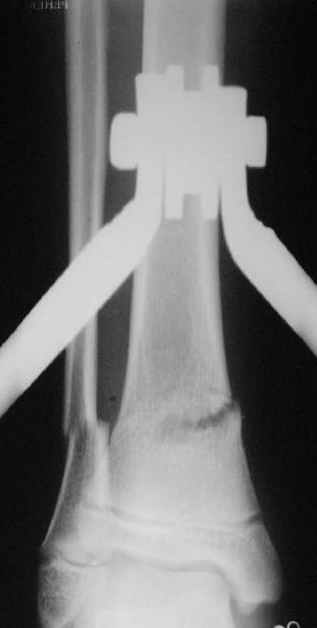

В январе 2005: варусная деформация н\3 голени, болевой с-м, комбинированная контрактура г\стопного сустава, нейропатия м\берцового нерва сохраняется слабость разгибания 1 пальца.

Операции: 1 Клиновидная резекция на вершине деформации м\берцовой кости.

2 Тугоподвижный ложный сустав н\3 б\берцовой кости. Рубцы выполняющие пространство между отломками, канал проксимального отломка иссечены.

Одномоментное устранение деформации, остеосинтез Г-образной пластиной.

Пластика по Хахутову.

Фиксация

Промежуточный